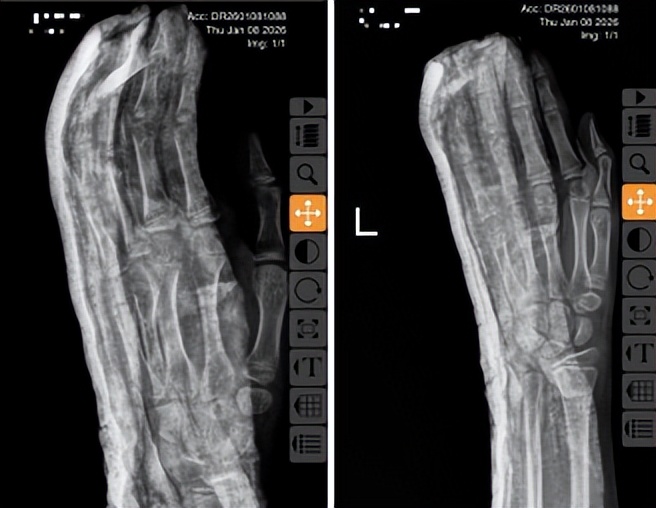

复位过程中,薛安邦主治医师凭借丰富的儿童骨折诊疗经验,在董博主任提出的“轻、柔、准、稳”技术指导下,于指间轻推慢移,精准把控着力道与角度,沉稳而柔和地将错位的骨块缓缓归位。整个操作短短几分钟便顺利完成复位,患指外形恢复正常,关节活动度显著改善。薛医师为小兰进行石膏外固定,并亲切叮嘱孩子要小手举高,便于快速消肿,同时向家长详细交代术后注意事项:“每天留意石膏松紧,如果手指发紫、发凉或者孩子喊麻,一定要马上来医院。”

术后复查X光片显示,骨折断端对位对线良好,达到理想复位标准。看到女儿疼痛缓解、手指恢复自然姿态,家长悬着的心终于放下,连连致谢:“多亏了你们的专业治疗,不然我们真不知该如何是好,太感谢红会医院的医生了!”